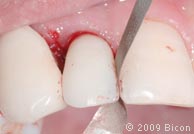

29. Удаление излишков мягких тканей, которые могут препятствовать правильной установке трансфера, производится посредством слепочного римера размером 3 мм, вращаемого вокруг направляющего штифта.

30. Коронка, зацементированная на правом клыке.